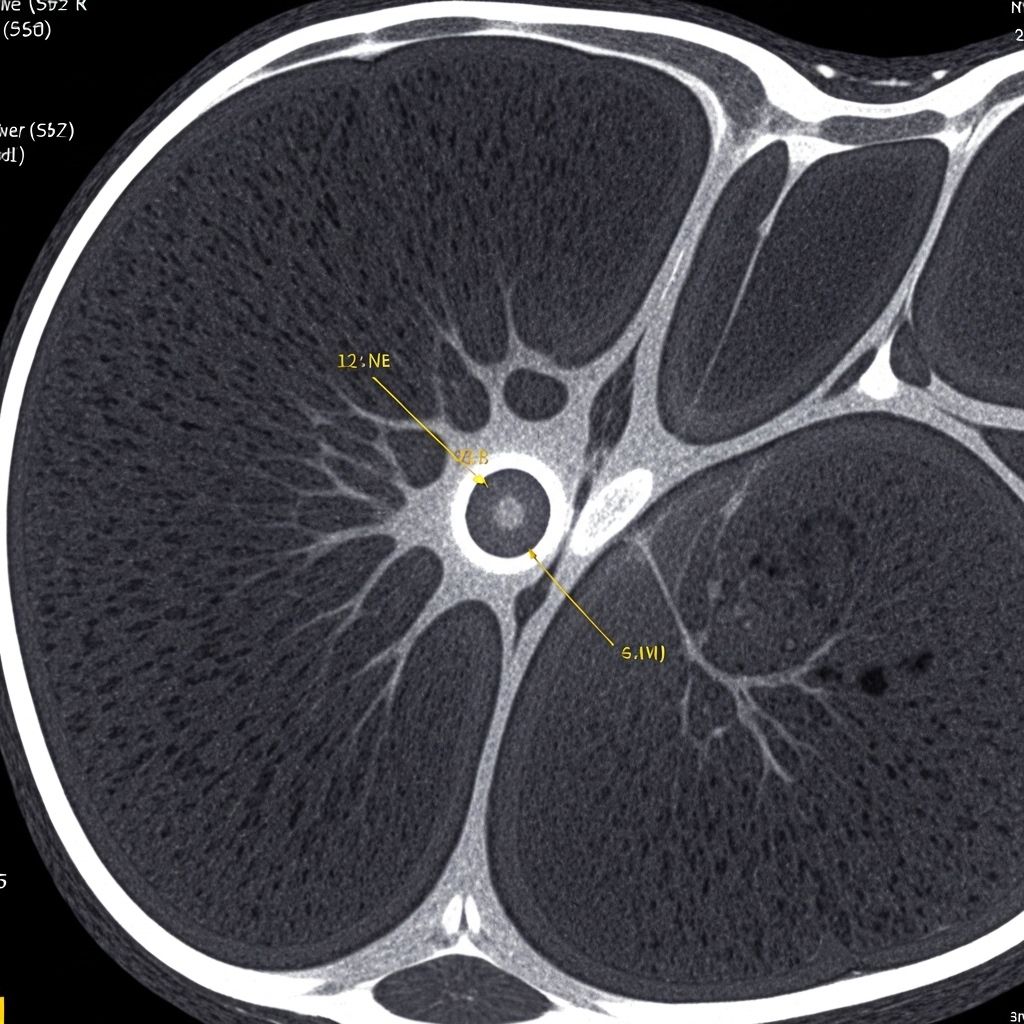

Lesión renal sospechosa

Procedimiento

Biopsia percutánea

Resultado

Diagnóstico histopatológico claro con mínima complicación

Recuperación

Paciente estable en 24 horas